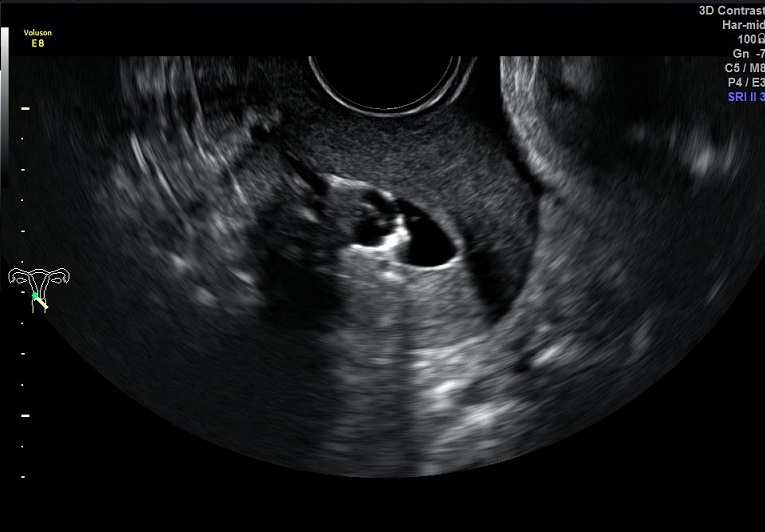

女性,30岁,继发性不孕2年,左侧输卵管宫外孕术后。常规二维超声子宫、卵巢及宫腔三维均未发现明显异常。宫腔置管后,宫腔水造影显示:宫腔稍见膨隆,内膜面光整,推注时有阻力。子宫输卵管实时三维超声造影显示:左侧输卵管未显示,右侧输卵管近端纤细,远端稍膨大,走行呈“S”行弯曲。诊断:左侧输卵管不通,右侧输卵管通而不畅。